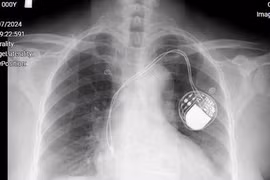

Đặt máy tạo nhịp cứu bệnh nhân tắc nghẽn đường dẫn truyền trong tim

Nhịp tim quá chậm do tắc nghẽn đường dẫn truyền trong tim là bệnh lý nguy hiểm gây ra các cơn choáng ngất, suy tim, thậm chí đe dọa tính mạng. Đặt máy tạo nhịp vĩnh viễn là kỹ thuật tiên tiến cứu giúp người bệnh.